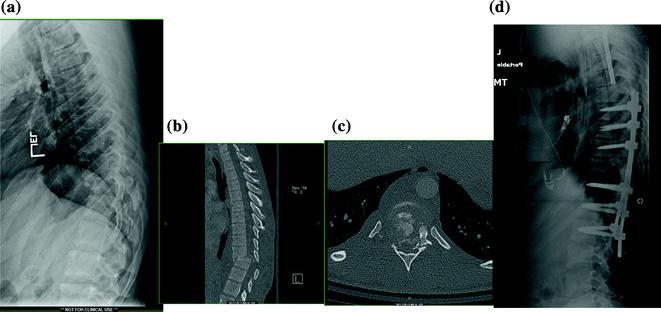

Fig. 17.1

a–c Preoperative CT scans of an unstable thoracic chance fracture, which is a flexion injury of the thoracic spine, demonstrated by the anterior vertebral body compression fracture with a transverse fracture through the posterior elements (blue arrows). d Postoperative radiograph showing treatment with posterior spinal instrumented fusion